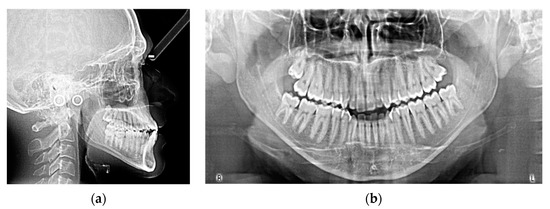

2. Case Report

| Measurements | Initial | Final | Norm |

|---|---|---|---|

| SNA (°) | 86.7 | 87.5 | 82.0 ± 3.5 |

| SNB (°) | 84.1 | 84.9 | 80.0 ± 3.5 |

| ANB (°) | 2.6 | 2.6 | 2.0 ± 2.5 |

| SN^ANS-PNS (°) | 7.2 | 6.3 | 8.0 ± 3.0 |

| SN^GoGn (°) | 37.7 | 37.7 | 33.0 ± 2.5 |

| ANS/PNS^Go-Gn (°) | 33.3 | 33.3 | 25.0 ± 6.0 |

| U1^ANS-PNS (°) | 113.2 | 111.8 | 110.0 ± 6.0 |

| L1^GoGn (°) | 85.1 | 80.4 | 90.0 ± 6.0 |

| L1 Protrusion (L1-APo) (mm) | 1.6 | 1.3 | 1.0 ± 2.5 |

| Overjet (mm) | 2.6 | 2.4 | 2.5 ± 2.5 |

| Overbite (mm) | 0.6 | 1.5 | 3.0 ± 2.5 |

| U1^L1 (°) | 131.1 | 136.4 | 135.0 ± 6.0 |

| Co-Go-Me (°) | 123.9 | 124.8 | 125.0 |

| Lower lip to Ricketts E-line (mm) | −4.8 | −5.6 | 0.0 ± 2.0 |